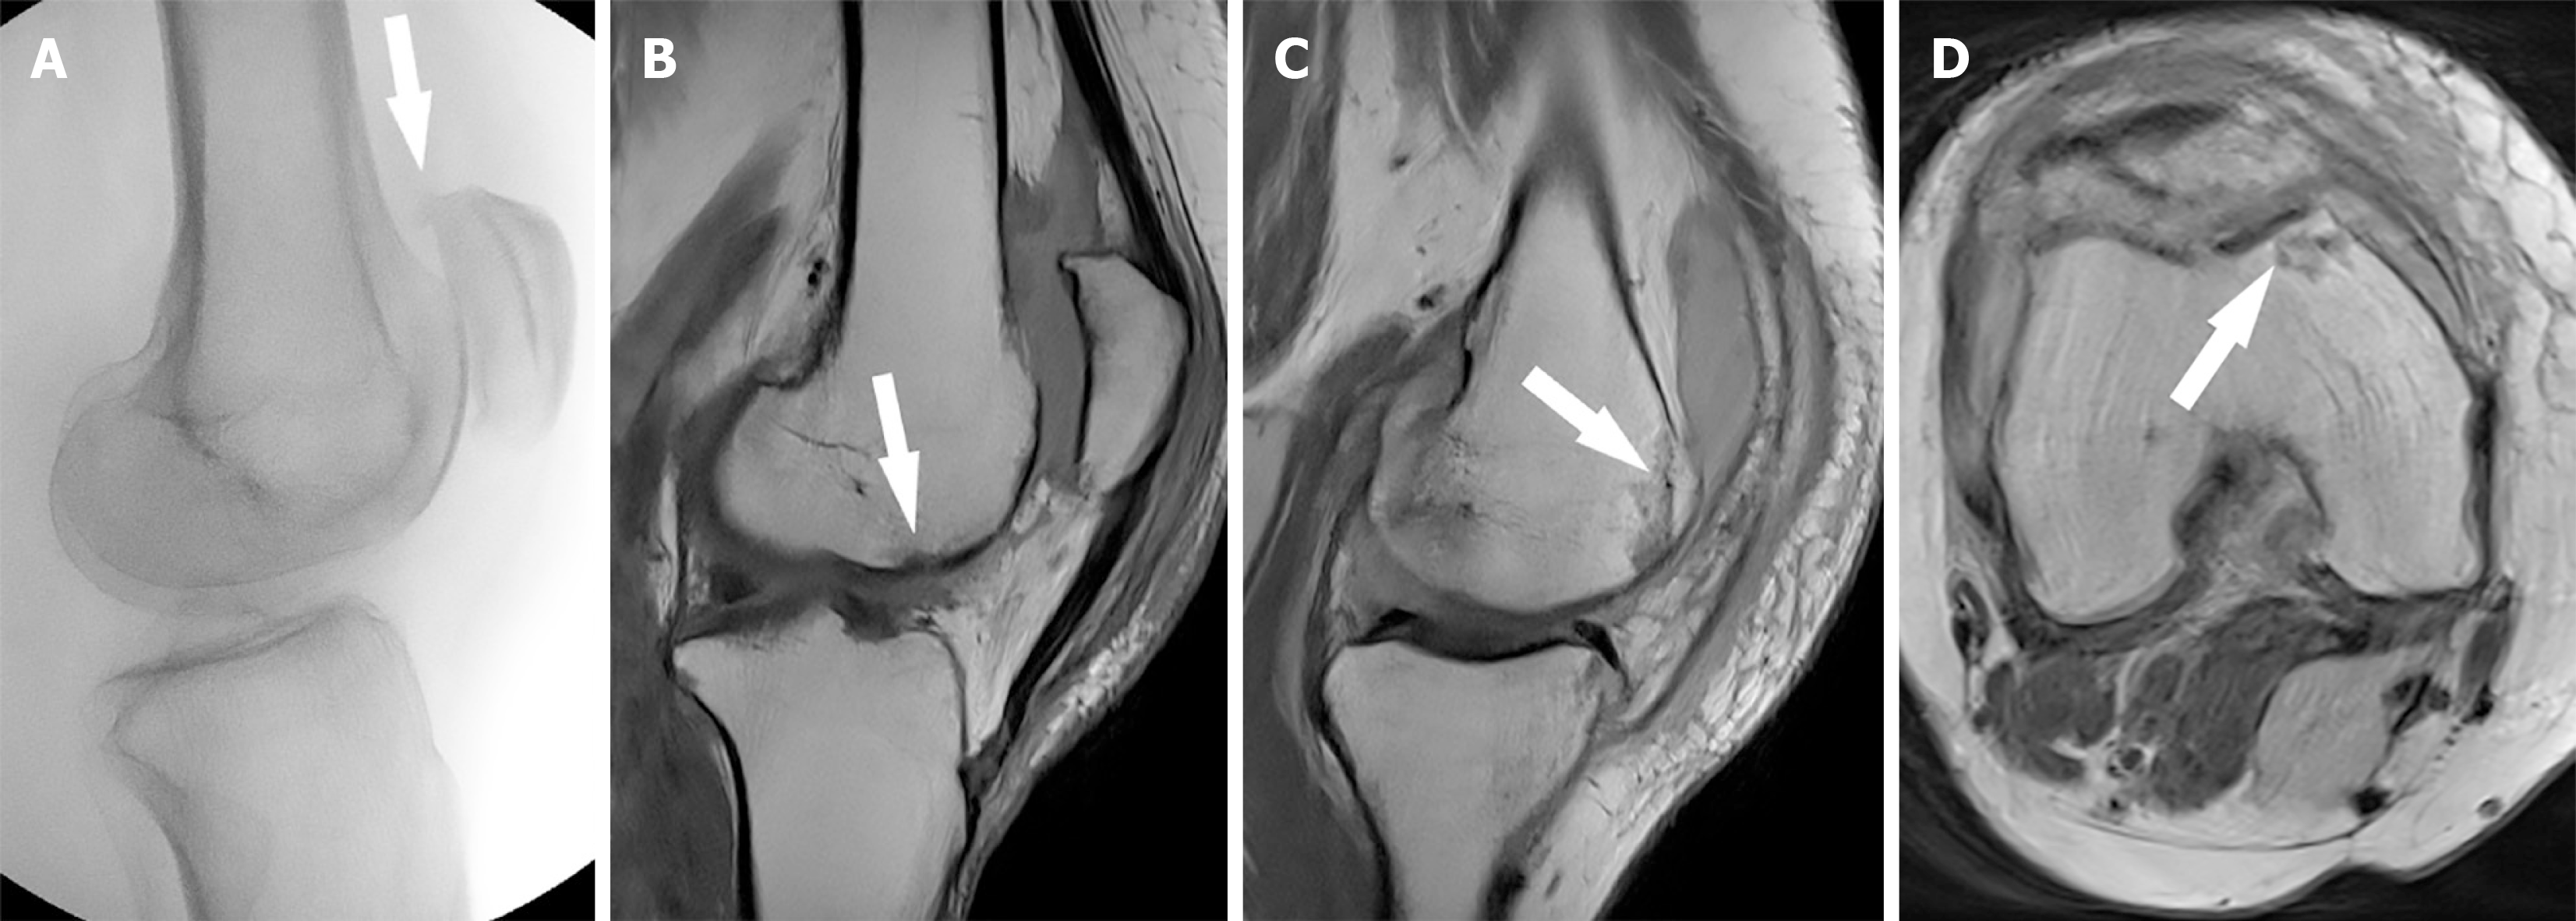

Figure 3 Intraoperative fluoroscopy and postoperative magnetic resonance imaging.

A: Intraoperative fluoroscopy confirmed reduction and showed a small superior patella osteophyte (white arrow); B: The sagittal postoperative magnetic resonance imaging (MRI) sequence redemonstrates the small femoral trochlear osteochondral fracture (white arrow) and confirms an intact extensor mechanism; C: Sagittal MRI sequence demonstrating a nondisplaced osteochondral fracture (white arrow); D: Axial MRI sequence demonstrating a nondisplaced osteochondral fracture (white arrow).